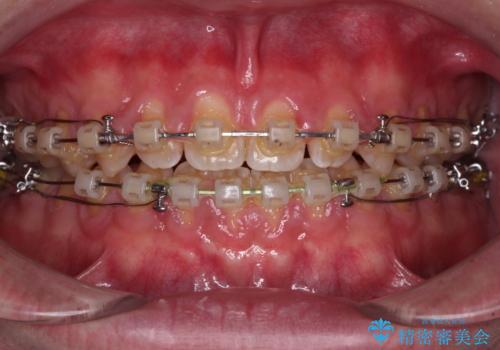

- 矯正装置

- クリアブラケット

- 治療期間

- 3年2ヶ月

舌の突出癖がなかなか改善されず、治療期間は当初予定よりも大分長くなりました。

装置除去を予定していた日に、油断されたのか1mmほどのスペースを作ってしまったため、除去が3ヶ月延長されたことで、舌のトレーニングの重要性を理解していただきました。